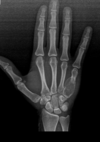

Fratura de Chaffeur

Fratura do processo estilóide do rádio.